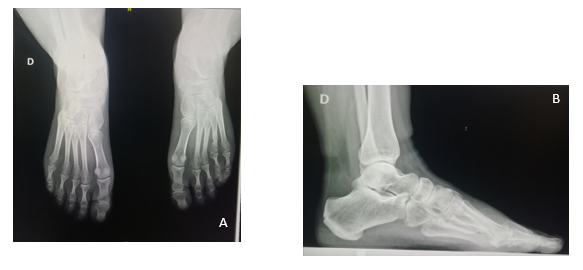

Figura 1: A y B: frente y perfil. Presentación clínica del paciente. Se observa una braquimetatarsia del cuarto radio.

En la radiología se observa un cuarto metatarsiano hipoplásico bilateral, sin afectación de las falanges. Este es curvo, no presenta subluxación de la articulación metatarsofalángica. Dicha articulación no ofrece alteraciones degenerativas artrósicas. Se constata la interrupción de la parábola metatarsal (Figura 2) Según la clasificación radiográfica de Lamm es 4A. 3

Figura 2: Radiografía de frente. Se constata la alteración de la parábola metatarsal mayor en el pie izquierdo. Un cuarto metatarsiano corto, subluxación de la articulación metatarso falángica.